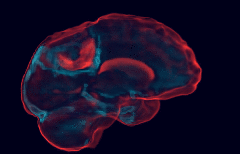

Creating Glioblastomas Atlases

Statistical Altas : [Roux, 2019] Frequence of apparition by voxels.

Anatomical Atlas : [Beg and Khan, 2005] Average shape.

Topological Altas : Collection of homeomorphisms covering a topological space (ex: manifold)